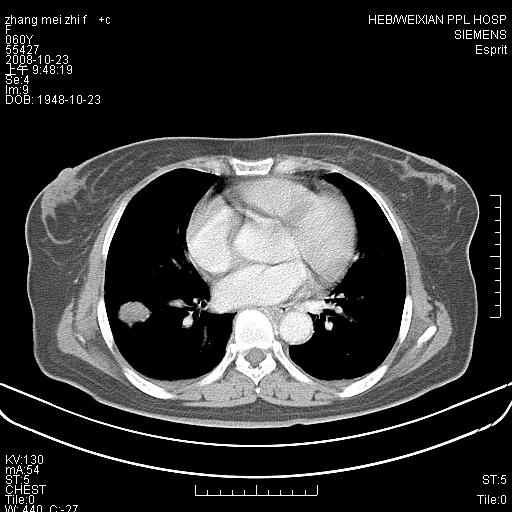

强化扫描后病灶几乎无增强,强化后的病灶看起来密度虽高,是我为了清晰改变了窗宽窗位。(有点弄巧呈拙)

先对现有的图象资料谈几点看法:病变位于右肺下叶前基底段,上部呈类圆形改变,分叶及毛刺征象不明显,下部呈不规则气腔改变,近肺门侧可见与一粗大血管相连,考虑为引流静脉影.其他肺叶相对正常所见.分析:该病灶良恶性均有可能.(现有资料来说).强化及穿刺活检有助鉴别.

我认为必须有纵隔窗资料;且最好做增强ct检查。现在发言为时过早***